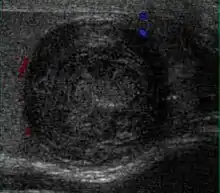

Patients with testicular lymphoma are usually old aged around 60 years of age, present with painless testicular enlargement and less commonly with other systemic symptoms such as weight loss, anorexia, fever and weakness. Bilateral testicle involvements are common and occur in 8.5% to 18% of cases. At sonography, most lymphomas are homogeneous and diffusely replace the testis [Fig. 7]. However focal hypoechoic lesions can occur, hemorrhage and necrosis are rare. At times, the sonographic appearance of lymphoma is indistinguishable from that of the germ cell tumors [Fig. 8], then the patient's age at presentation, symptoms, and medical history, as well as multiplicity and bilaterality of the lesions, are all important factors in making the appropriate diagnosis.

Primary leukemia of the testis is rare. However, due to the presence of blood-testis barrier, chemotherapeutic agents are unable to reach the testis, hence in boys with acute lymphoblastic leukemia, testicular involvement is reported in 5% to 10% of patients, with the majority found during clinical remission. The sonographic appearance of leukemia of the testis can be quite varied, as the tumors may be unilateral or bilateral, diffuse or focal, hypoechoic or hyperechoic. These findings are usually indistinguishable from that of the lymphoma [Fig. 9].

Fig. 9. Leukemia. Diffuse hypoechoic infiltrative lesions are seen involving the whole testis, indistinguishable from that of the lymphoma.